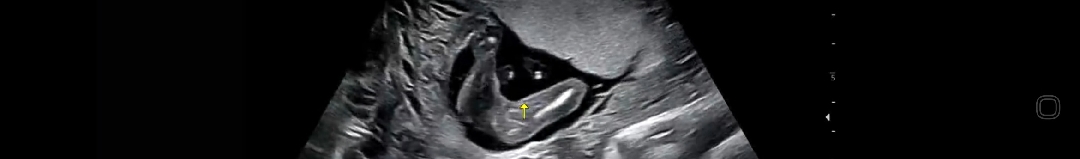

안녕하세요 16주 빼박 딸이죠??

선생님께서도 딸인거 같다 해주셨는데 빼박이죠???

매끈하네요 ㅎㅎ